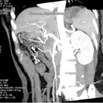

Pancreatic Coronal

显示胰腺冠状面影像